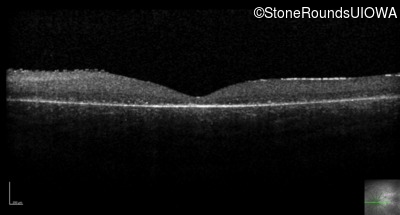

Optical Coherence Tomography - Left - 10/160 sc

Exemplar / OCT Stack